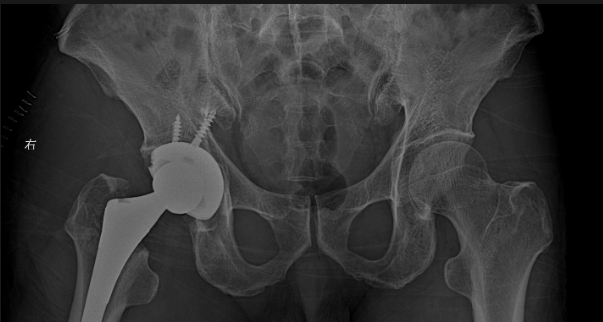

65岁的孙大伯,走路时不慎滑倒摔伤,值班医生马上为大伯做了检查,发现右股骨颈骨折;还有81岁的李爷爷,作为体育爱好者,在骑自行车锻炼的时候一不当心摔伤,检查结果也是右股骨颈骨折。两人就相隔一天,都相继入住康华医院骨2科。

孙某 ——男——65岁

经过术前检查评估,两位老人都做了人工全髋关节置换术。手术过程顺利,第2天就已经可以下地活动行走。病人和家属的脸上也一扫前几天的阴霾,露出了开心的笑容。